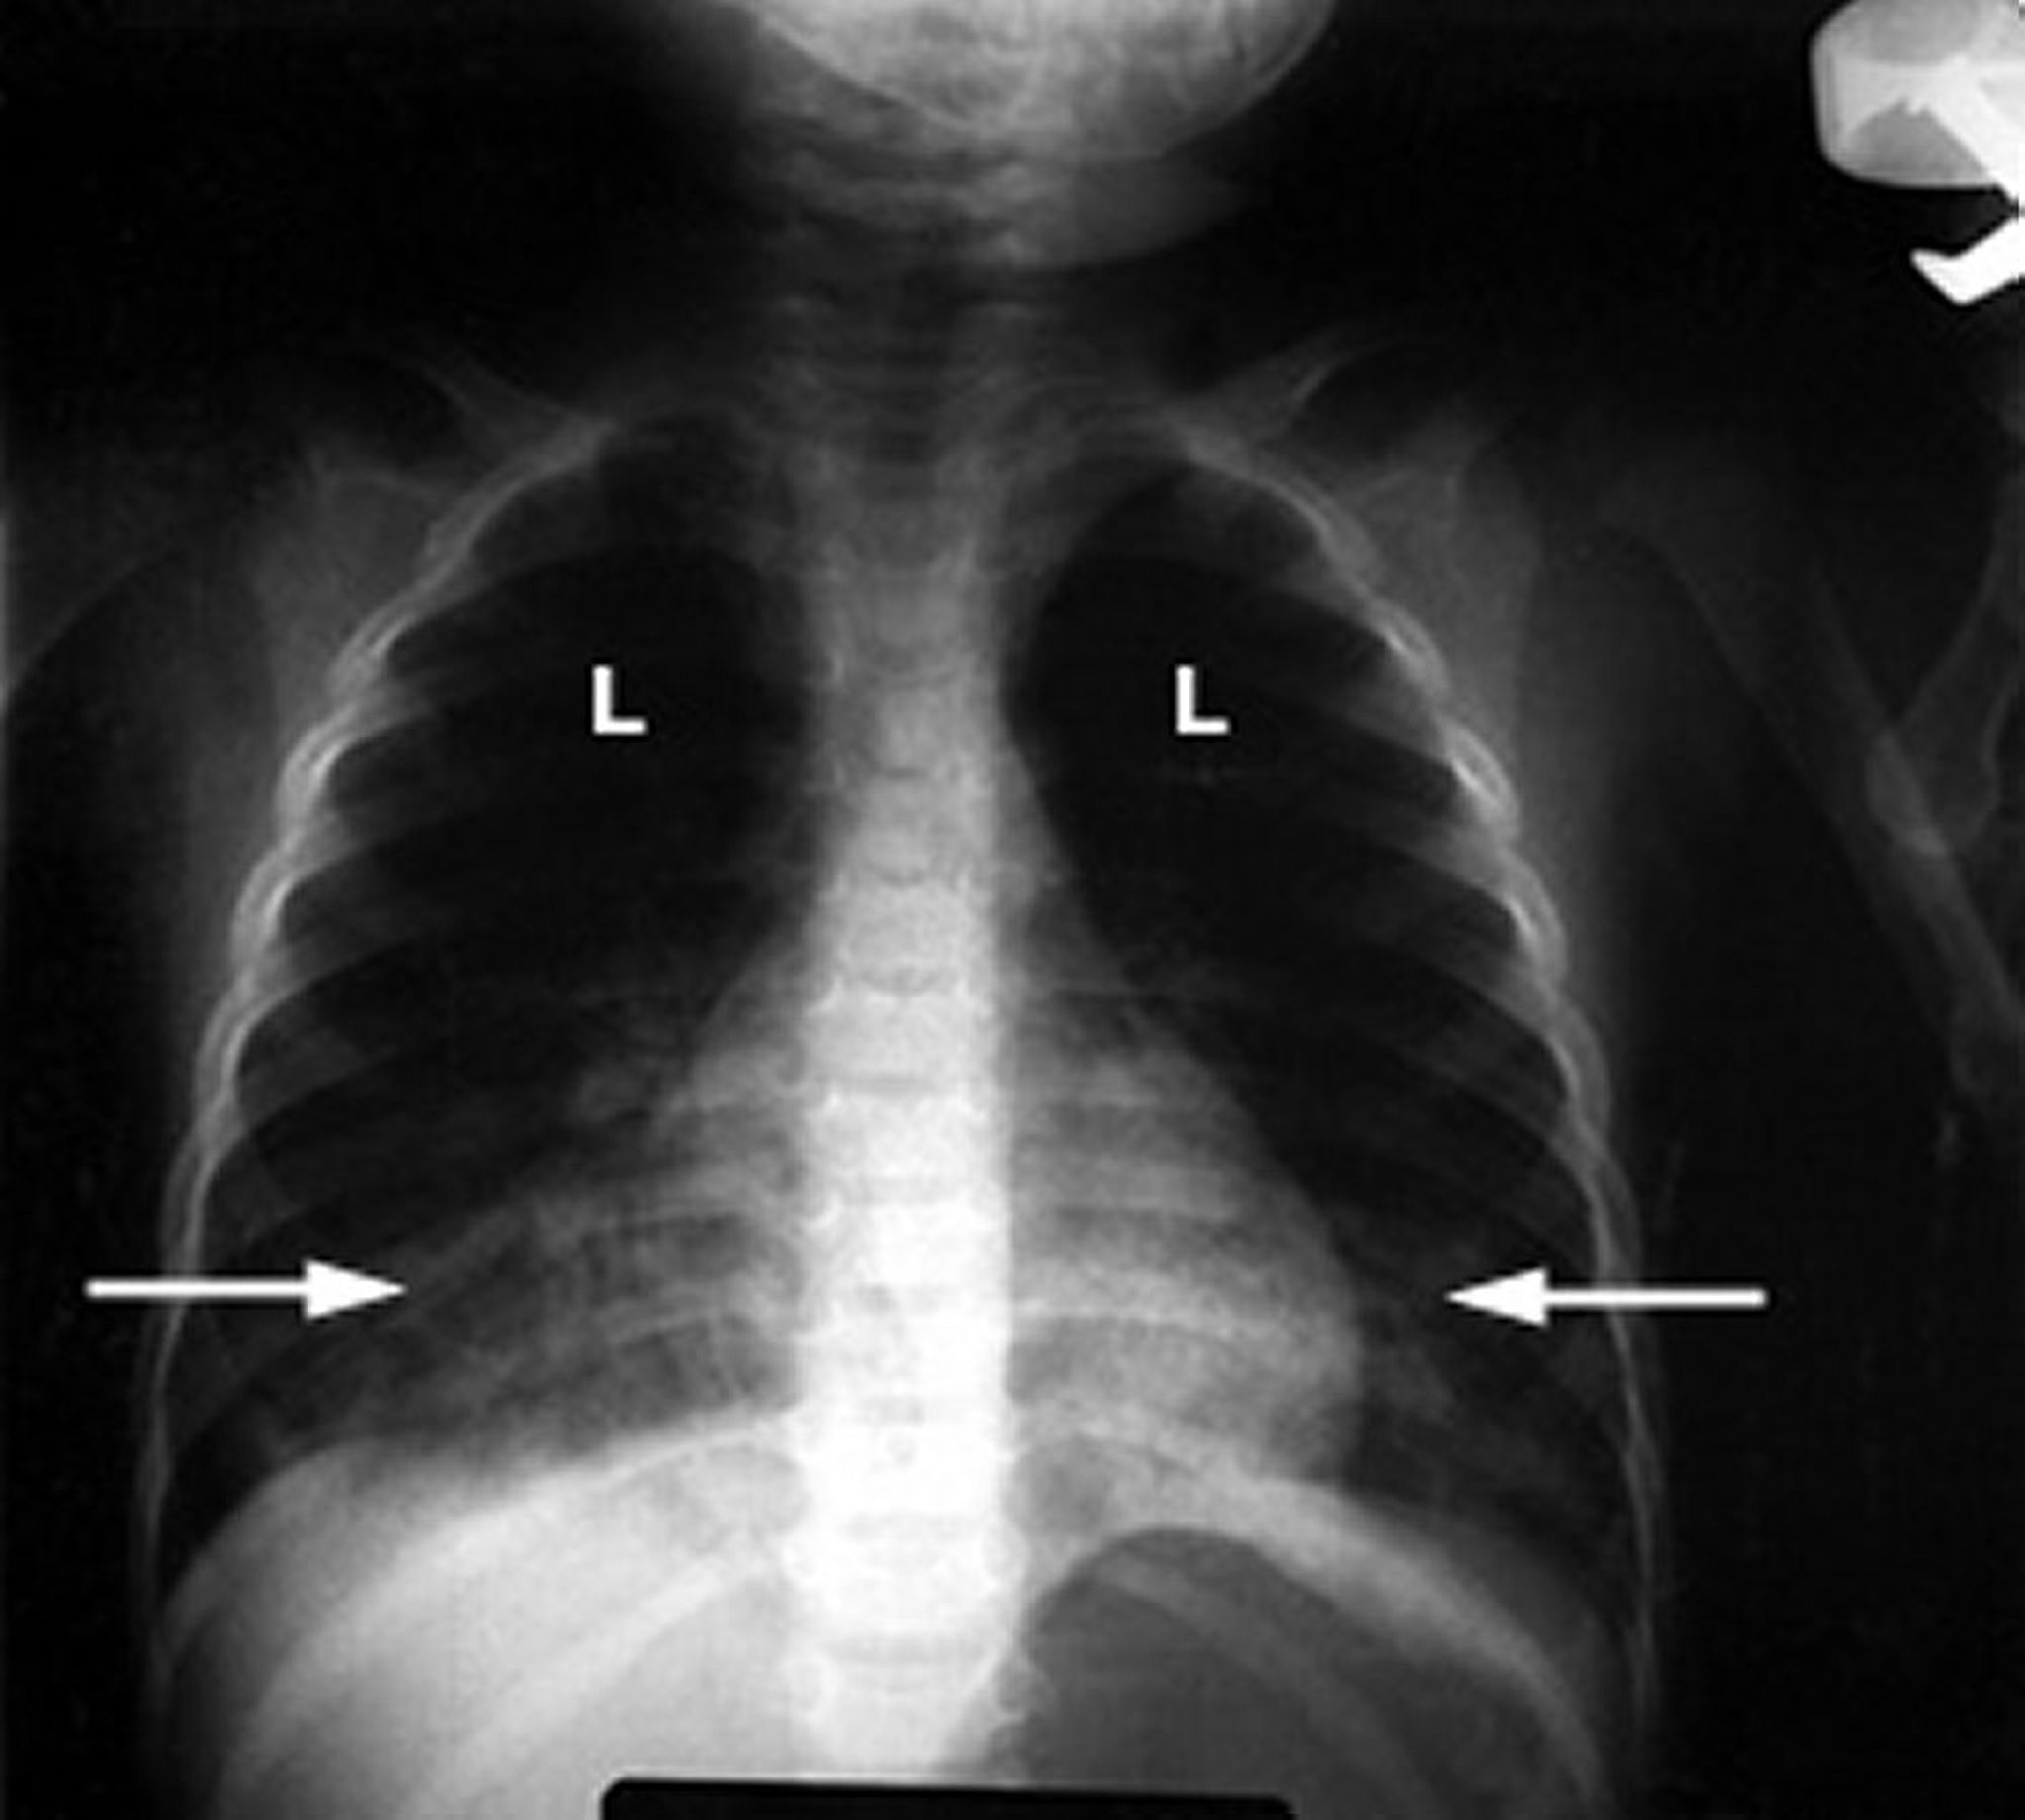

हाइड्रोकार्बन को सांस में लेने के कारण होने वाला रासायनिक न्यूमोनाइटिस

शिशु में एक असामान्य छाती का एक्स-रे फेफड़ों (L) में सफेद फल्फी इनफिल्ट्रेशन (तीर) दिखाता है, जो सूजन का संकेत देता है। यह खोज हाइड्रोकार्बन विषाक्तता के कारण फेफड़ों की क्षति के लिए विशिष्ट है।

जी. श्मिट, MD के सौजन्य से।